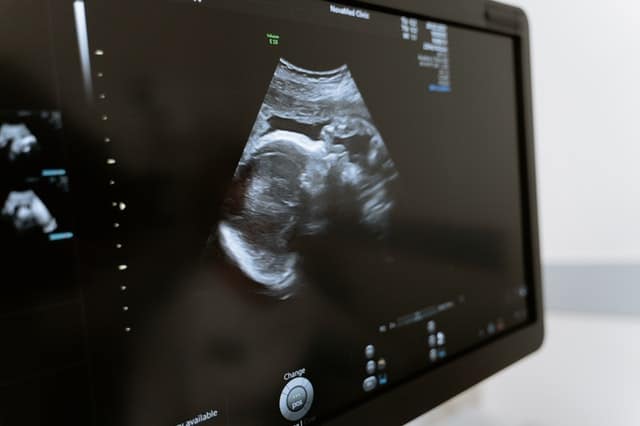

אין מקרים פשוטים בכל הקשור אל רשלנות רפואית, אך כנראה שהמסובכים מכולם הם תיקים של רשלנות רפואית בהריון ובלידה שני תחומים אשר מן הסתם מקושרים זה לזה. במהלך הריון, ועוד לפניו – בייעוץ הגנטי – אישה הרה פוגשת אנשי רפואה רבים מתחומים שונים: רופאי נשים, מומחי אולטרסאונד, מומחי גנטיקה ופריון, אחיות, מיילדות ועוד.

בנוסף, היא עוברת שורה של בדיקות וסקירות. כל זה נועד להבטיח הריון תקין ואת בריאות האם והעובר, אך למרבה הצער לעיתים זה לא מספיק. לא ניתן להגדיר כל נזק שנגרם במהלך ההריון או הלידה בתור רשלנות רפואית בהריון. רשלנות רפואית בהיריון תוגדר רק כאשר רמת הטיפול חרגה מסטנדרטים רפואיים סבירים. כלומר, ניתן להגיש תביעות רשלנות רפואית רק אם יוכח כי אנשי רפואה אחרים היו פועלים אחרת, במקום המעורבים במקרה.

בכל שלבי ההריון, על הגורמים השונים לפנות נשים לבדיקות (שגרתיות או מעבר לזה), להסביר לגביהן, לפענח אותן בצורה מדויקת ולמסור את התוצאות להורים. אם נמסרות להם תוצאות תקינות, והן שגויות, זה כמובן מצביע על רשלנות רפואית בהריון.